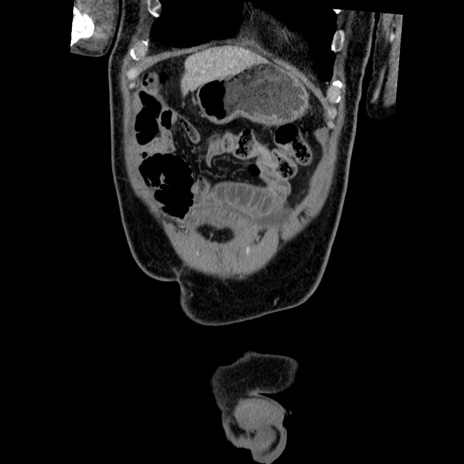

症例22(冠状断像)

【症例】50歳代男性

【主訴】腹痛

【現病歴】AVMからの被殻出血のため回復期リハ病棟入院中。 本日午後3時頃急に下腹部痛が出現した。

【既往歴】AVM、被殻出血、虫垂炎、高血圧

【身体所見】意識晴明、左半身不全麻痺、会話の理解は良好、36.5°C、腹部:膨隆、全体に板状硬、下腹部正中に圧痛点あり、反跳痛-、筋性防御不明、右下腹部にope scar

【データ】WBC 9400、CRP 0.06